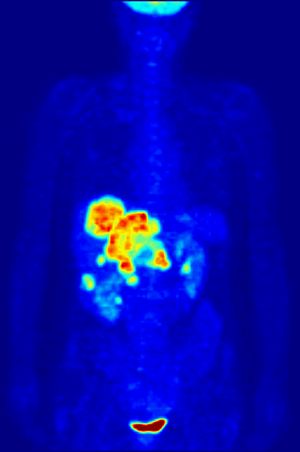

그 외 PET의 다양한 응용 분야는 다음과 같다.4. 1. 종양학

플루오로데옥시글루코스(FDG)를 이용한 PET 스캔은 임상 종양학에서 암의 진단, 병기 설정, 치료 반응 평가에 널리 사용된다.[4] FDG는 포도당과 유사한 물질로, 포도당 대사가 활발한 암세포에 많이 축적되는 성질을 이용한다.[4] 이러한 FDG의 축적 정도를 영상화하여 암의 위치와 크기를 파악할 수 있다.

FDG-PET는 특히 호지킨 림프종,[6] 비호지킨 림프종,[7] 폐암[8][9][10] 등 다양한 암종에서 활용된다. 2020년 연구에 따르면, 호지킨 림프종 환자의 중간 PET 스캔에서 음성 결과가 나오면 더 높은 전체 생존율 및 무진행 생존율과 관련이 있다는 증거가 발견되었다.[11] 다만, 이 증거의 확실성은 생존율에 대해서는 보통, 무진행 생존율에 대해서는 매우 낮았다.[11]